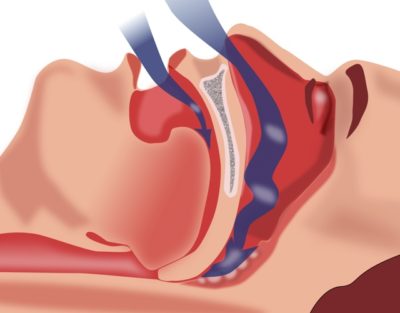

A legtöbb kábítószer és eszközök célja, hogy megerősítse az izmok a lágy szájpadlás és a torok, valamint a bővítés a légcső. Gyógyszerek aktívan tompítsa a nyálkás, meggátolja az váladék, nyugodt, megnyugtatja irritációt és fájdalmat.

Annak ellenére, hogy a hatékonyság, sem azonnali alapok nem megfelelőek a szindróma obstruktív alvási apnoe. És gyógyszerek segíteni:

A különböző mellbimbó. és kondenzátor beilleszti hasznos az égen gyenge szövetek hajlamosak a megszűnése. Szúr emelje fel őket, és tartani egy bizonyos helyzetben, bővíti a teret a szabad légzést.

- Sonayt. Capa képlékeny műanyag könnyen alkalmazkodik a harapás alakja. Nos rögzített a szájban, az nem esik, és nem törik el. A fő cél az eszköz: megakadályozására bomlás a falak, a garat és a szabad légzést.

Az eszköz megakadályozza, hogy a ragasztás az ég, bővülő a légcső, megakadályozva rezgése izmokat. Szükség van-függőség, nincs ellenjavallat. Ár 750 rubelt.